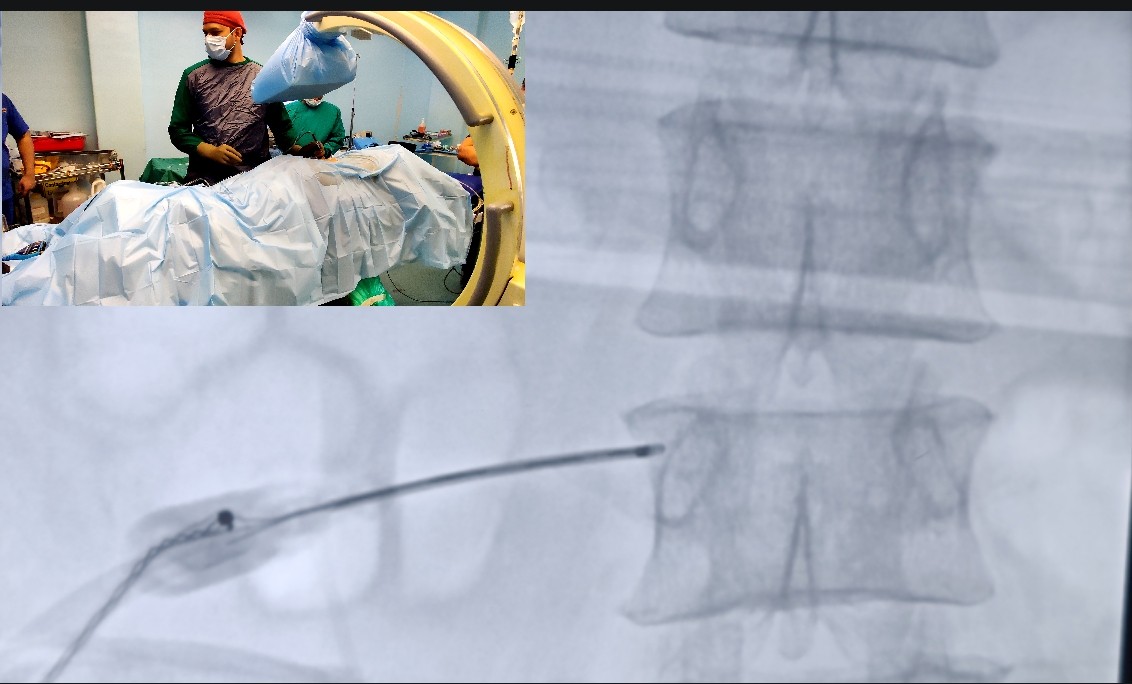

Radiofrequency ablation is a highly advanced and minimally invasive treatment modality used in patients of chronic pain. Currently practiced by only Pain physicians in India, It involves use radiofrequency ( high frequency) waves which are delivered around the problematic nerves of the joints with the help of specially designed needles at a predetermined intensity and time.

• Minimally invasive technology involving only use of needles